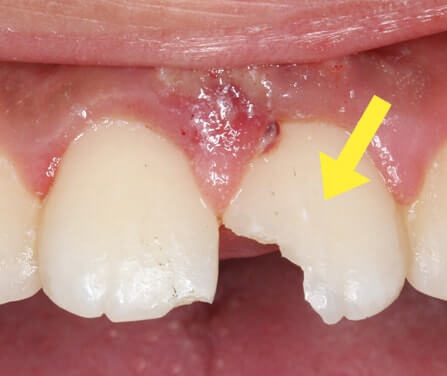

歯の外傷(転んだり、ぶつけたりして歯が欠けてしまった、抜けてしまった)